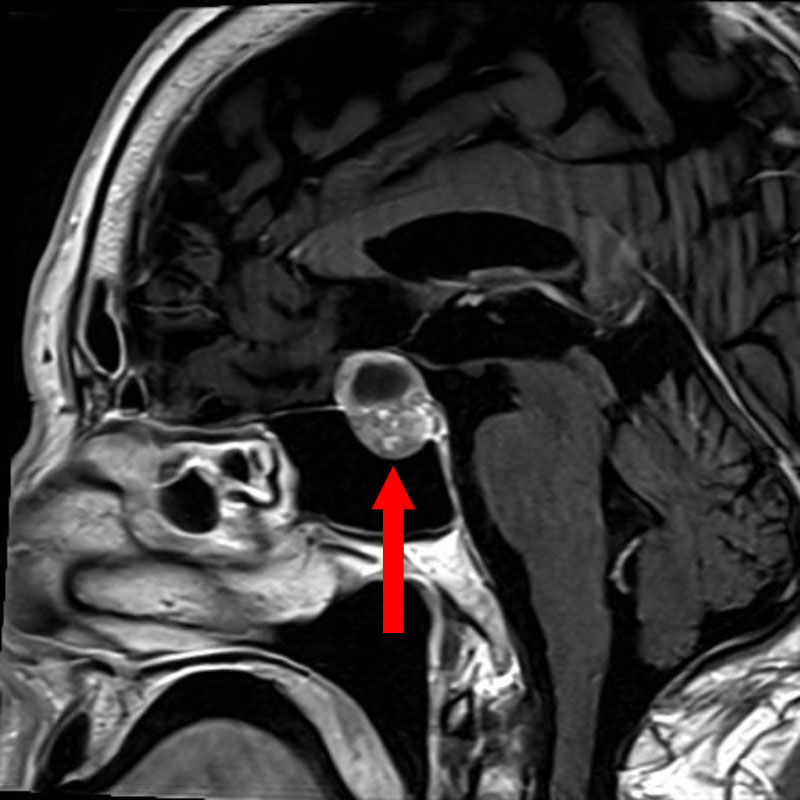

下垂体腺腫

頭蓋内腫瘍摘出術

No.’25_107 手術前1

No.’25_107 手術前2